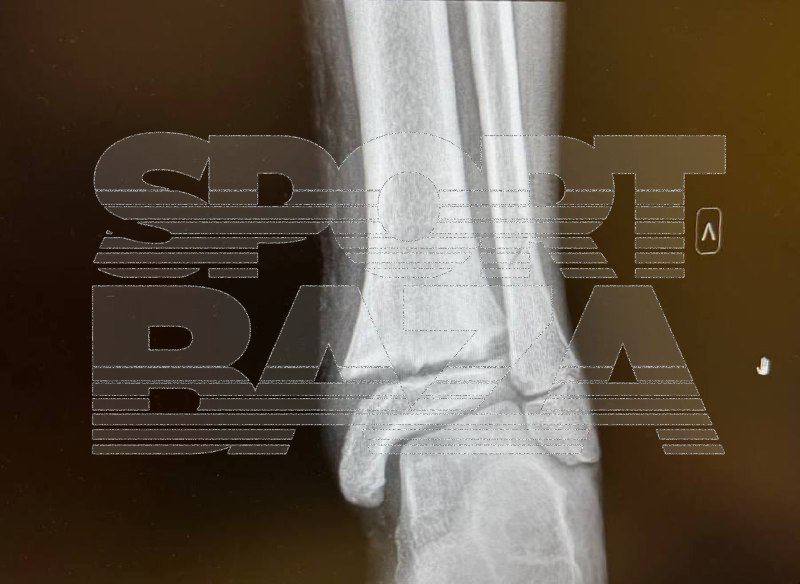

В Подмосковье подросток самбист умышленно покалечил соперника на тренировке Как сообщает Телеграм канал Baza все произошло в Мытищах Юный самбист 12 лет сломал ногу сопернику во время тренировки не взирая на крики других подростков и призывы тренера не проводить болевой прием Предыстория ЧП такова Миша и Дима имена изменены занимающиеся в одной секции пару недель назад поссорились Миша въехал в друга Димы на велосипеде Дима решил ему отомстить во время отработки болевого приёма Он взял и просто выполнил прием в полную силу После случившегося тренер помазал пострадавшему больное место мазью и попросил мать Миши забрать его с занятия В больнице у мальчика диагностировали переломы малой и большой берцовых костей со смещением Сейчас Миша передвигается в инвалидной коляске Мать мальчика направила в спортшколу судебную претензию и подала заявление в полицию